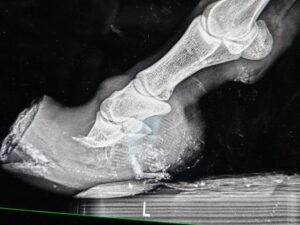

It was for our little red friend we worried the most. Hooves like hers don’t grow overnight, and the reality of what living with hooves like those does to a horse’s anatomy is at best, manageable, and at worst, unlivable. She was incredibly nervous, and required a very patient, quiet touch to allow us to sedate her for the radiographs we needed to understand what we were working with. Her small buddy accompanied her to where they had set up the x‑ray station, and stood patiently nearby as we peered under the hood.

The films revealed the depth of damage that walking on imbalanced, overgrown hooves for extended periods can do. The tips of her coffin bones were remodeling, and her hooves were severely unbalanced, with a long and deep abscess track in one of her hinds. Despite these findings, the vet was of the opinion that it might be possible to keep her and her friends comfortable with significant rehabilitation, and that all four horses were fit enough to join us back at SAFE.